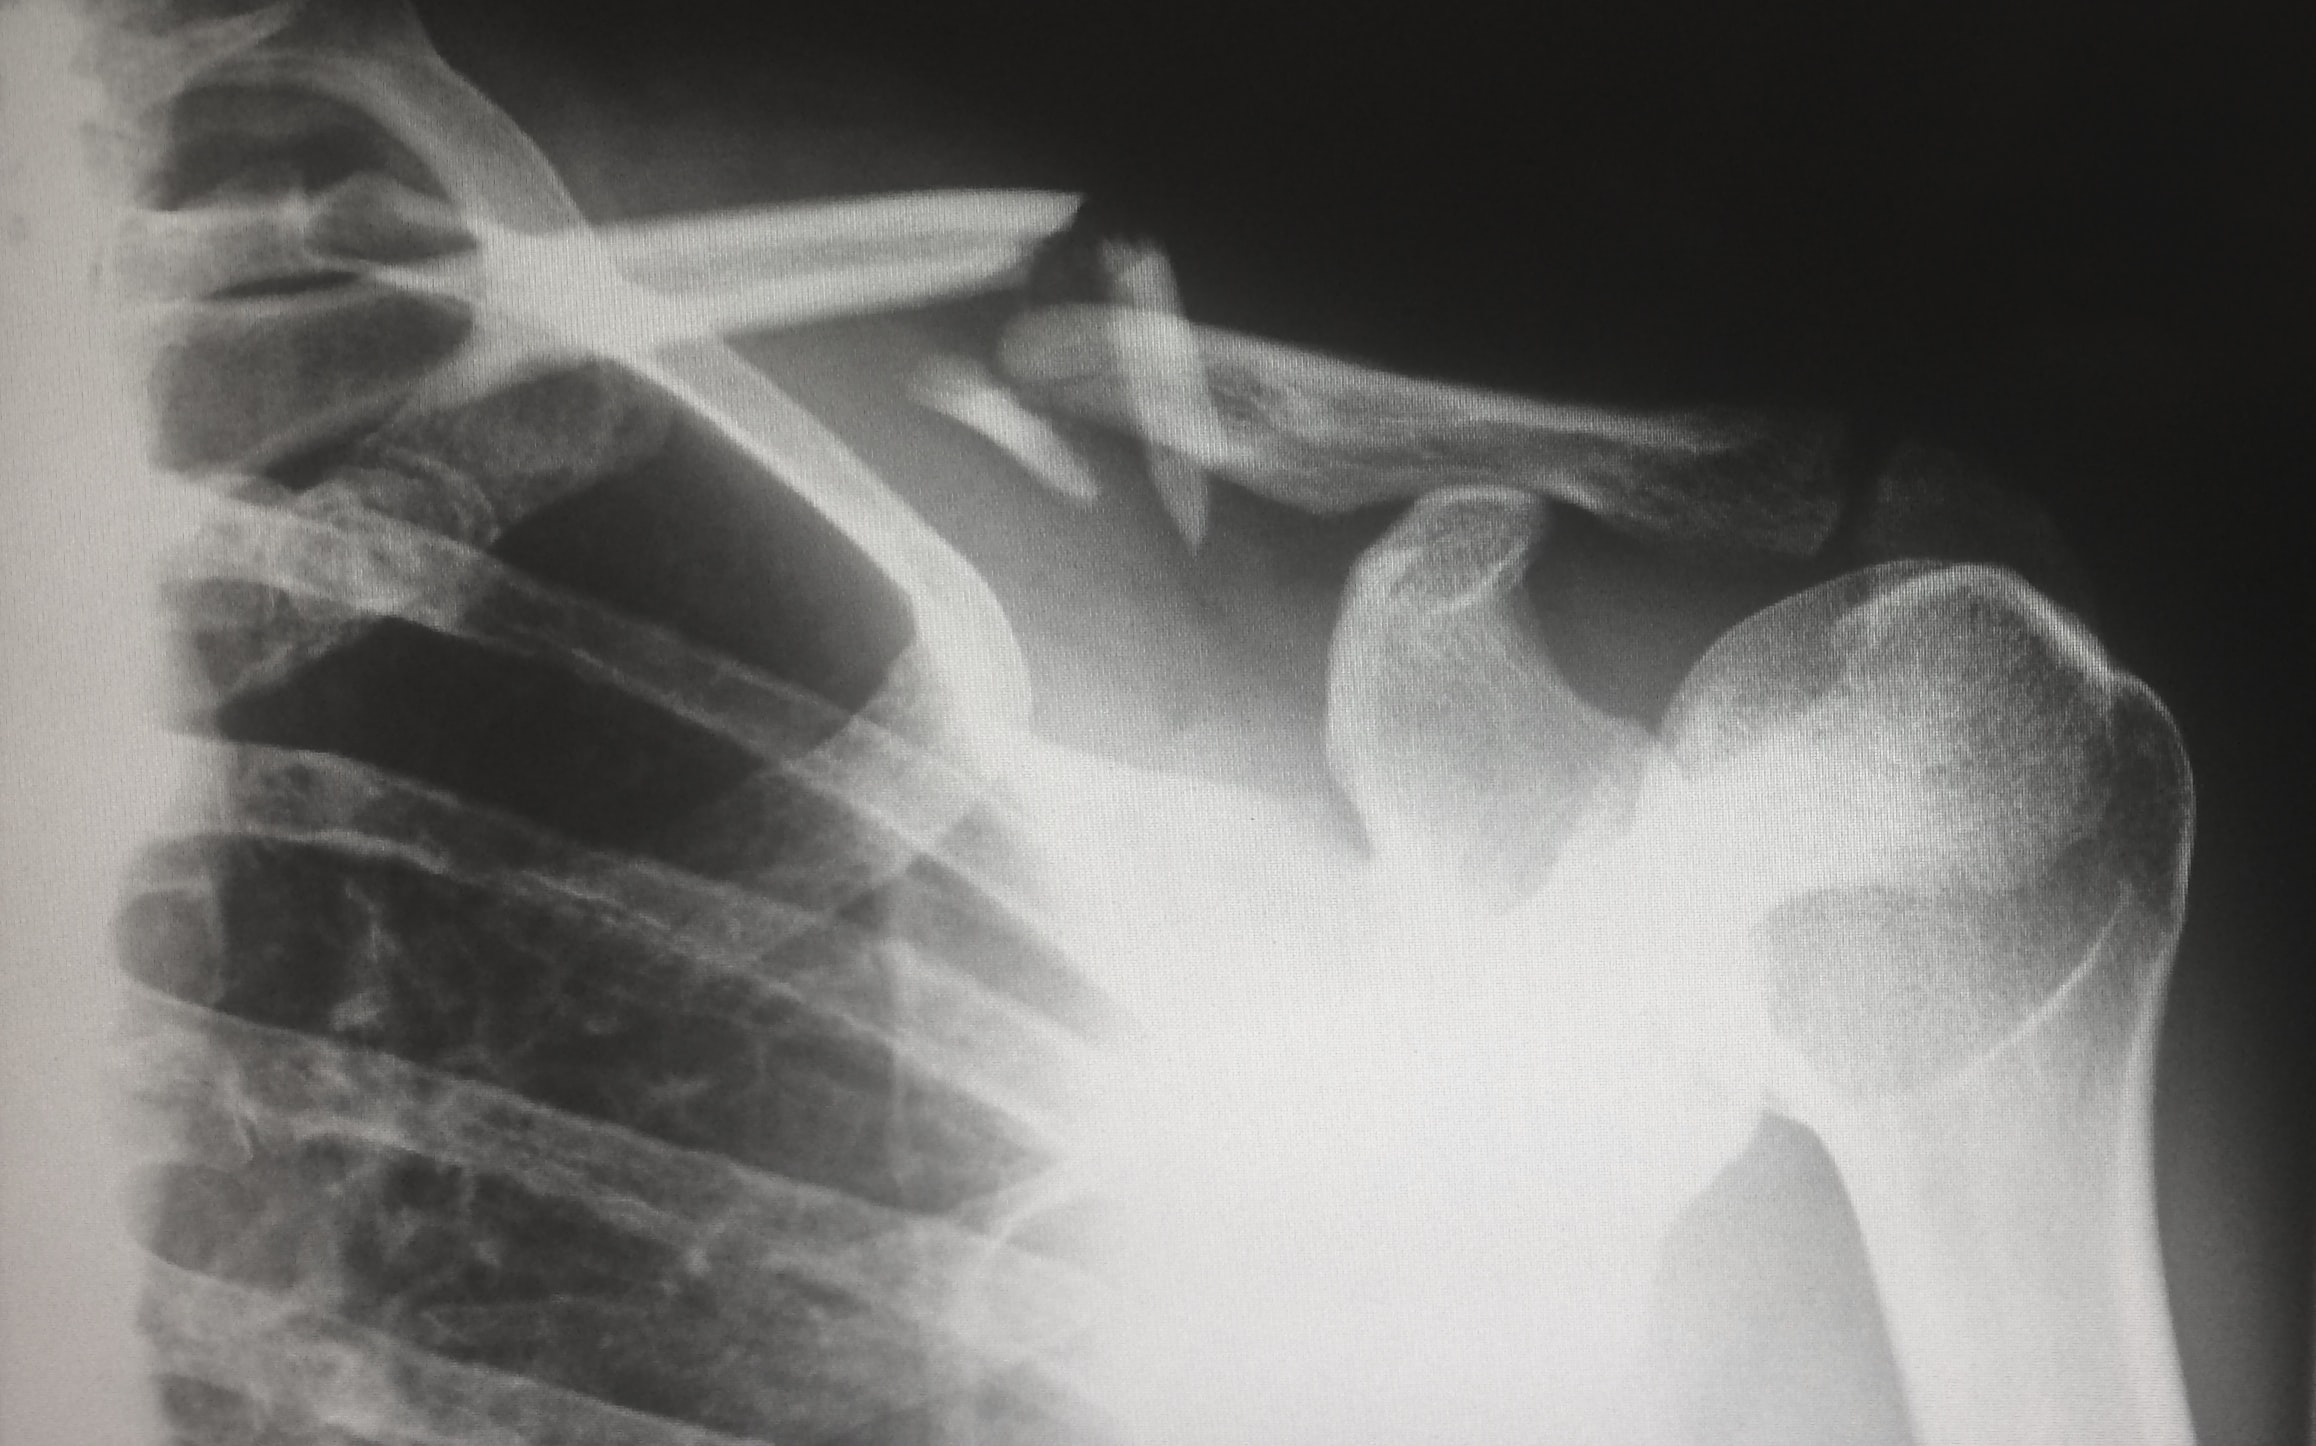

석회성건염

석회성건염은 나이대가 좀 있는 분들이 걸리기 쉬운데요. 혈액순환 장애로 인해서 어깨 힘줄에 석회가 침착되는 과정에서 힘줄과 근육을 자극해서 생기는 질환입니다.

이것도 어깨를 여러 방향으로 움직일 때 심각한 통증을 발생시키고 특히 자려고 누웠을 때 어깨가 찌릿하면서 통증을 느낀다면 석회성건염일 가능성이 많습니다. 누웠을 때 우리 체중이 어깨로 쏠리게 되면서 석회가 힘줄을 자극하면서 어깨통증 원인이 됩니다.

엑스레이 검사를 통해 자세히 진단해볼 수 있으니 위와 같은 증상이 나타나면 바로 적절한 치료를 시작하시기를 바랍니다. 보통은 약물치료와 체외충격파 치료를 병행하면서 금방 호전이 되기는 하나 심해지면 수술이 불가피할 수 있으니, 초기에 대처하시길 바랍니다.